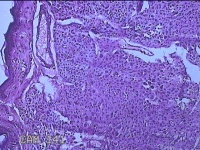

右腋下肿物

性别

女

年龄

28岁

临床诊断

纤维瘤病;皮肤感染

一般病史

无

标本名称

大体所见

灰白粉红色肿物0.3x0.2x0.1cm一个,表面光滑。

制片不太好,看看有没有核分裂,感觉是个皮内痣,问题不大